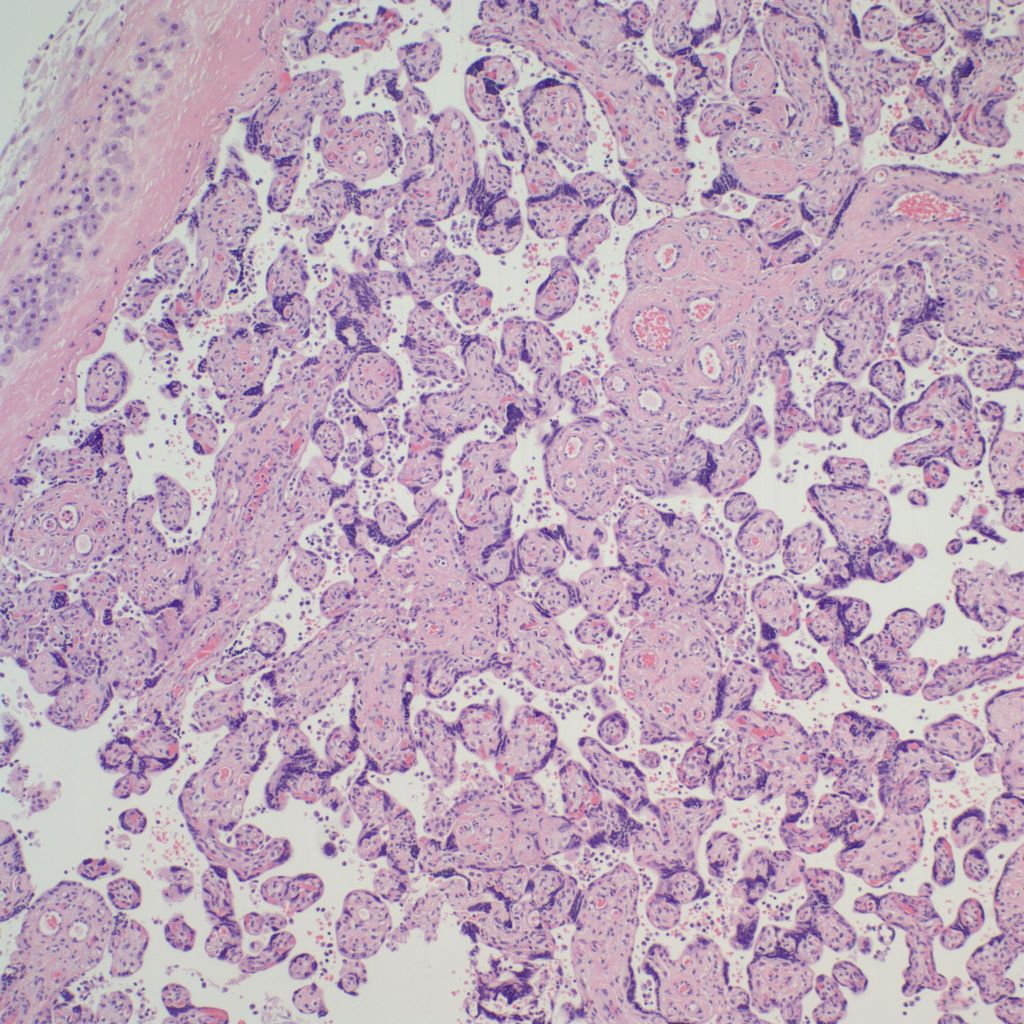

Low Grade CHIV (5-50% of the intervillous space occupied by monocytes)

Microscopic criteria: The primary criterion is monocytes clustered in the intervillous space which can be confirmed by CD 6810,17. The monocytes often have kidney bean shaped nuclei and prominent cytoplasm. Some other consensus criteria are that the inflammatory cells in the intervillous space should be at least 80% monocytes, and these should be maternal cells1,17.

Extent and Severity: If this is an untreated case, one accepted criterion is that the monocytes occupy 5% of the sampled intervillous space. The severity can also be graded usually as less than versus more than 50% of the intervillous space filled with monocytes. The number of monocytes in the largest clusters, and whether the distribution is evenly distributed or focal may also be useful observations.